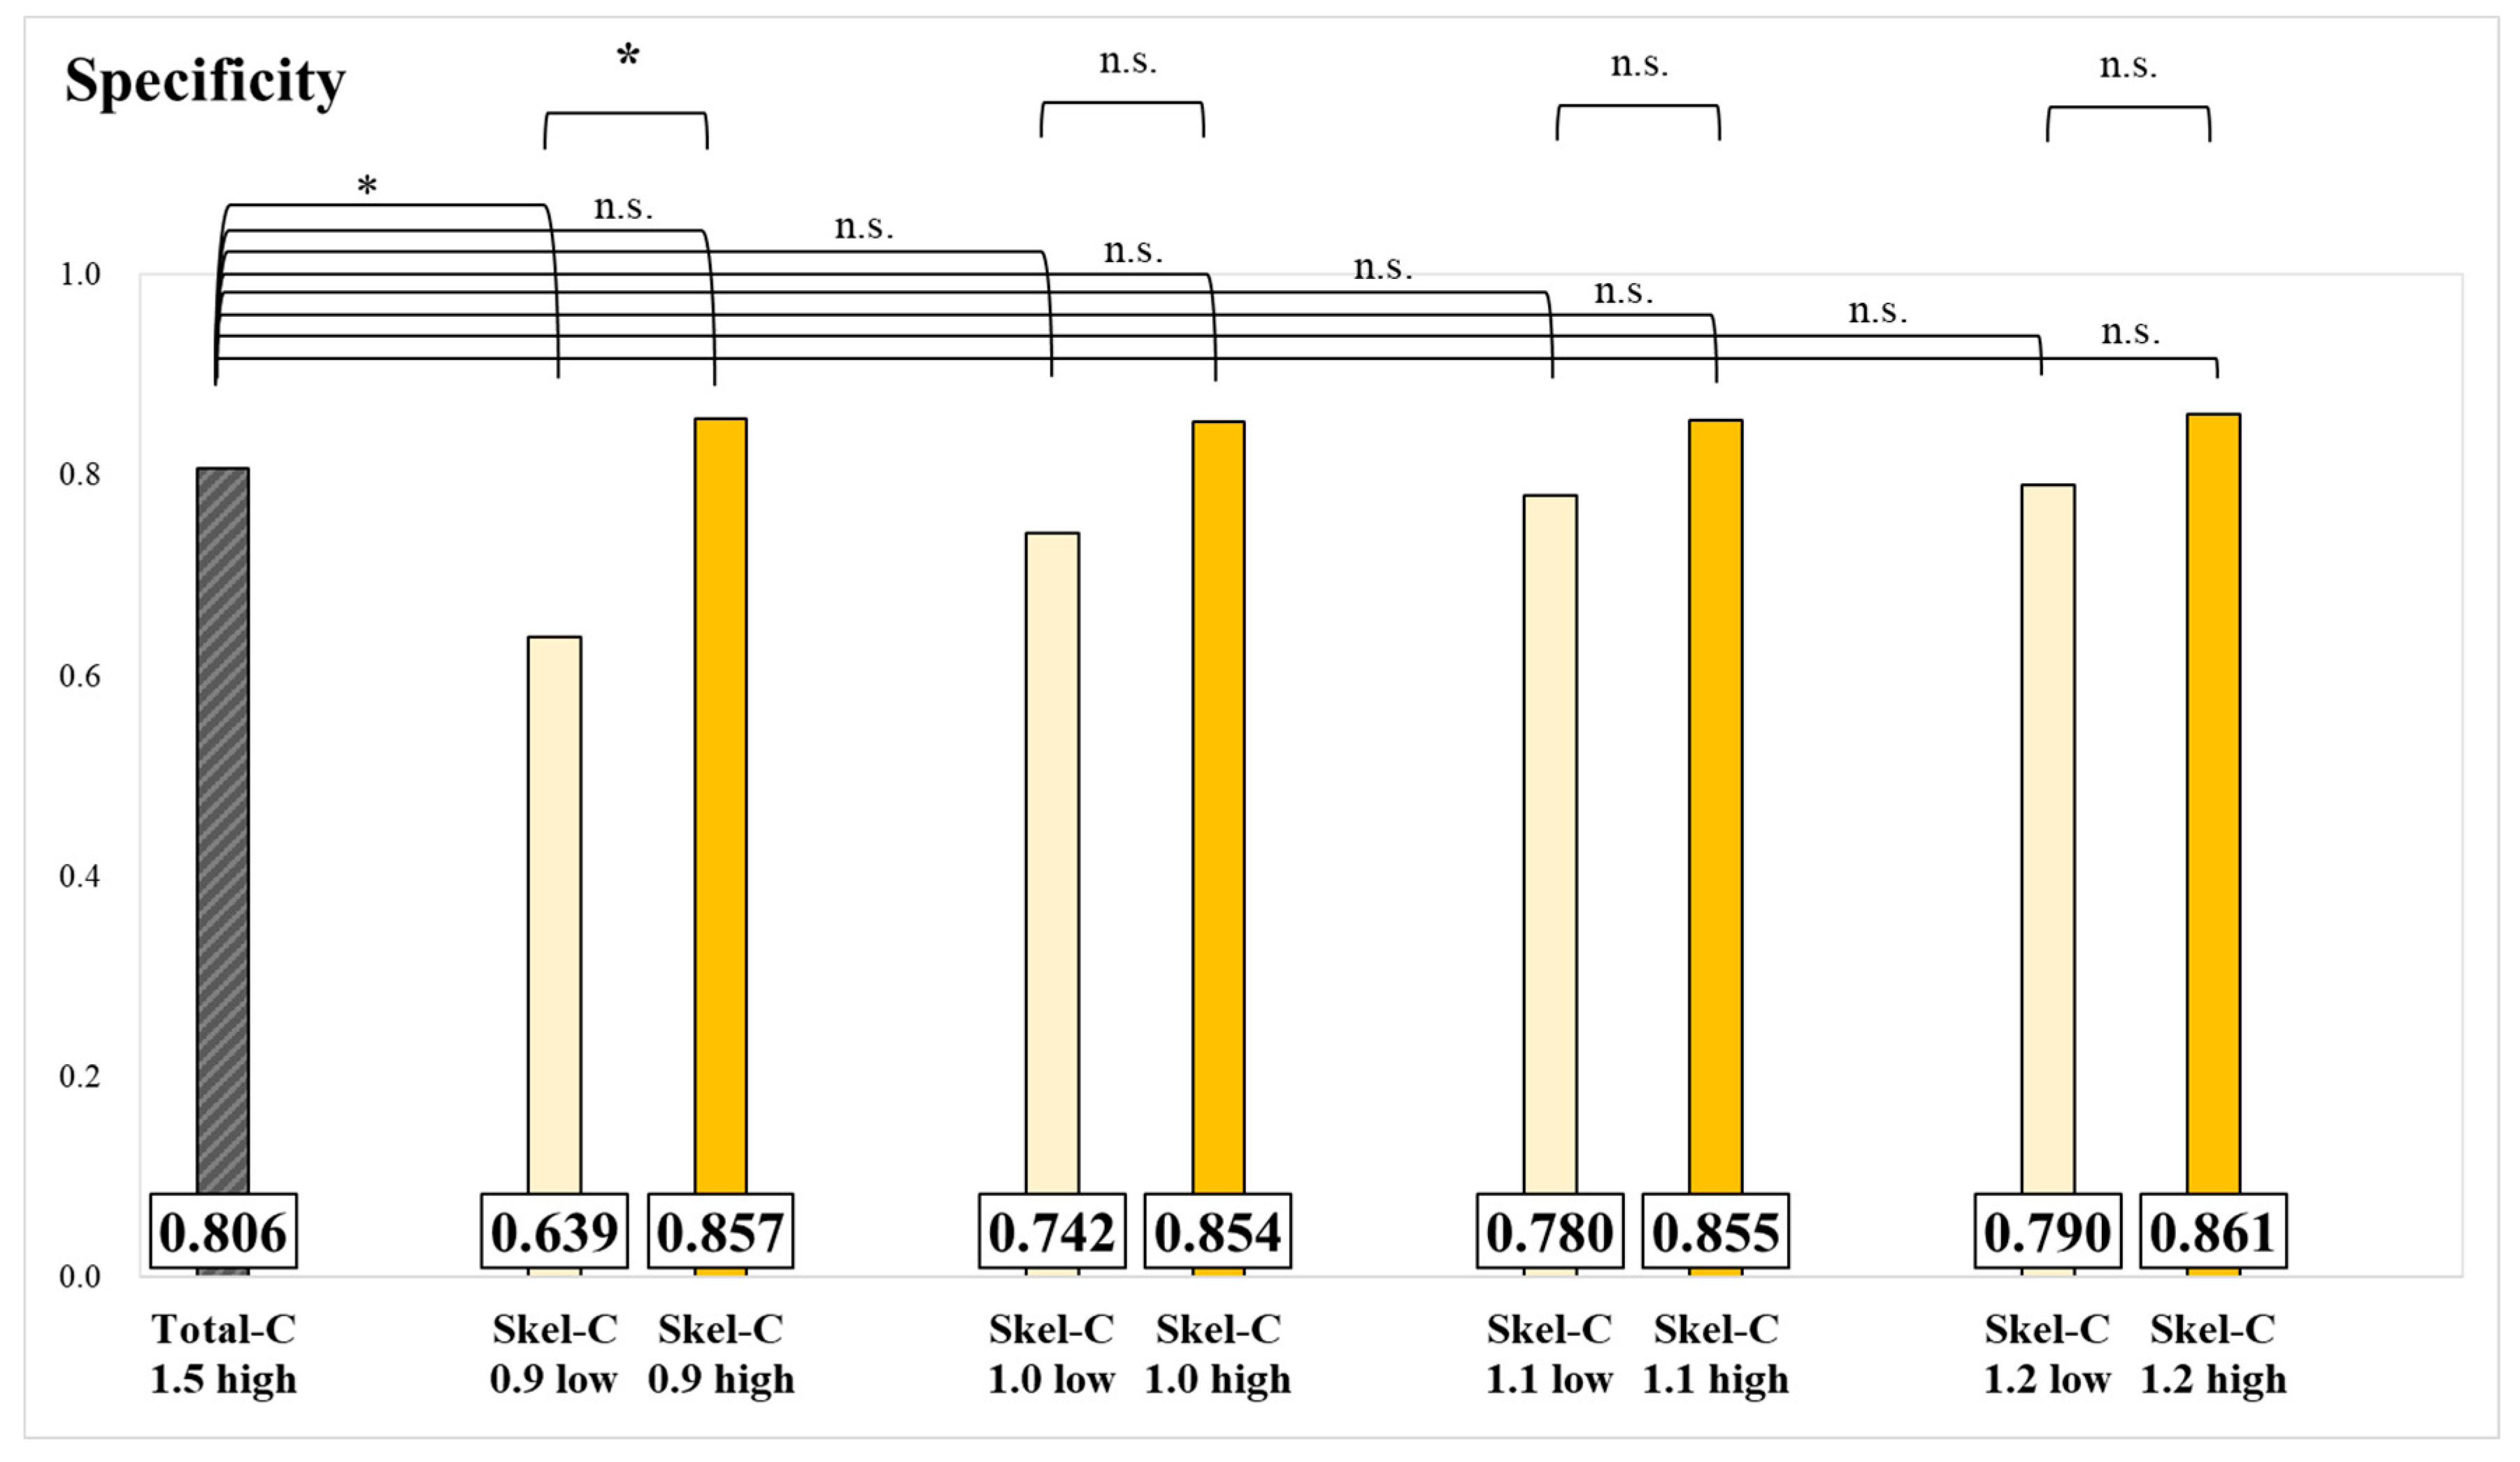

3. Results

4. Discussion

| Skel-C 0.9 low | 42 | 6 | 36 | 755 | 3.93 |

| Skel-C 1.0 low | 87 | 21 | 66 | 757 | 3.83 |

| Skel-C 1.1 low | 137 | 37 | 100 | 752 | 3.84 |

| Skel-C 1.2 low | 167 | 48 | 119 | 753 | 3.82 |

| Skel-C 0.9 high | 194 | 75 | 119 | 751 | 3.73 |

| Skel-C 1.0 high | 149 | 60 | 89 | 749 | 3.72 |

| Skel-C 1.1 high | 99 | 44 | 55 | 751 | 3.66 |

| Skel-C 1.2 high | 69 | 33 | 36 | 747 | 3.63 |